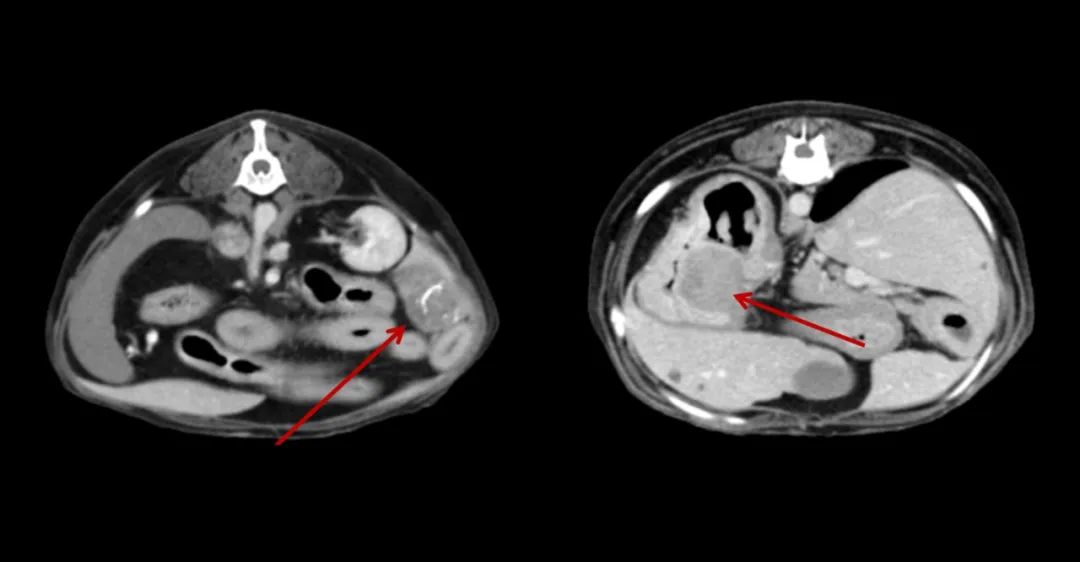

▲7歲,38kg的金毛狗近期總是嘔吐,CT全身平掃+增強(qiáng),發(fā)現(xiàn)肝和胃占位性病變。